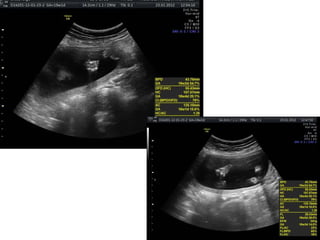

Cystic fibrosis

AR multisystem disorder: dysfunctional chloride ion transport

across epithelial surfaces

>1000 CFTR mutations possible

1/2000-5000

Best diagnostic clue:

Echogenic bowel in 2nd trimester progressing to bowel dilation

in 3rd trimester

Fetal echogenic bowel